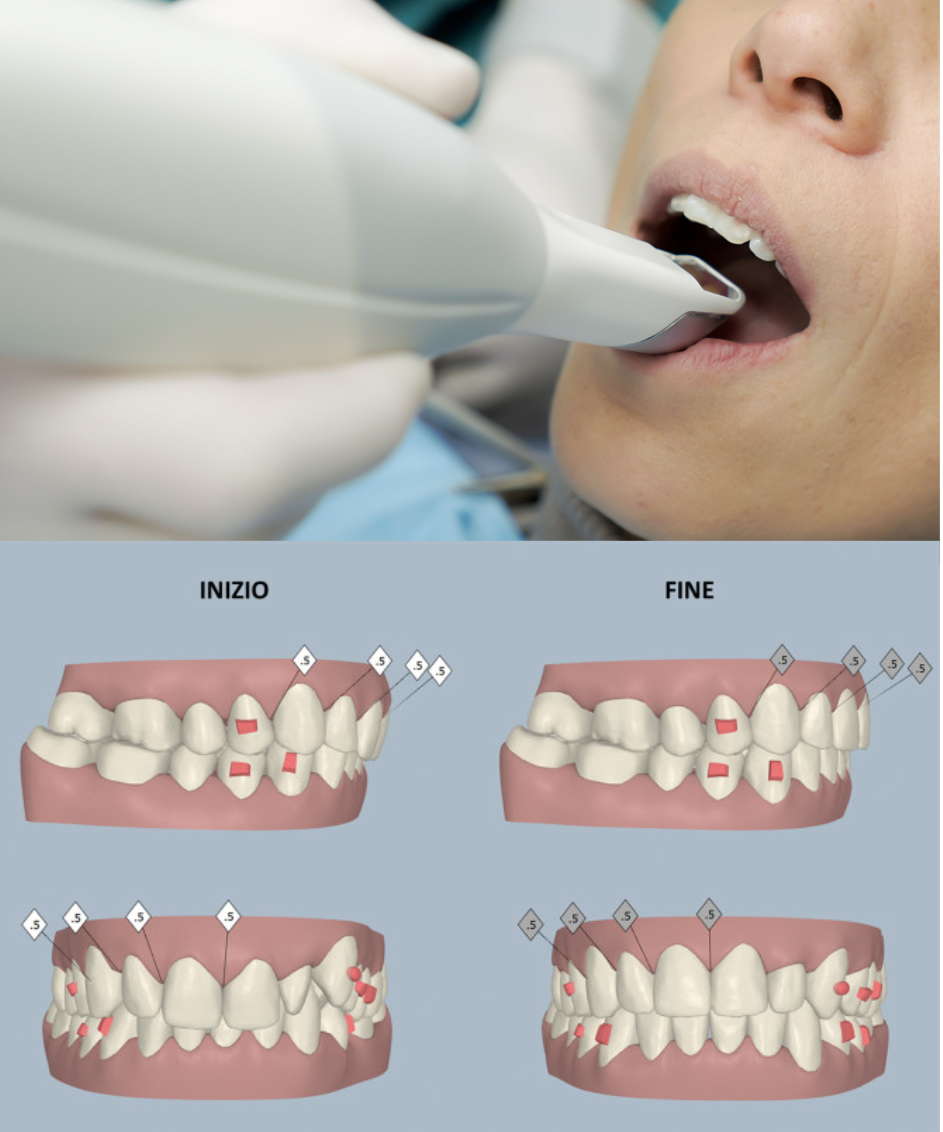

Da oltre 10 anni per realizzare questi obiettivi utilizzo le mascherine trasparenti, un eccezionale apparecchio ortodontico che non si nota ed in più è estremamente confortevole e rimovibile.